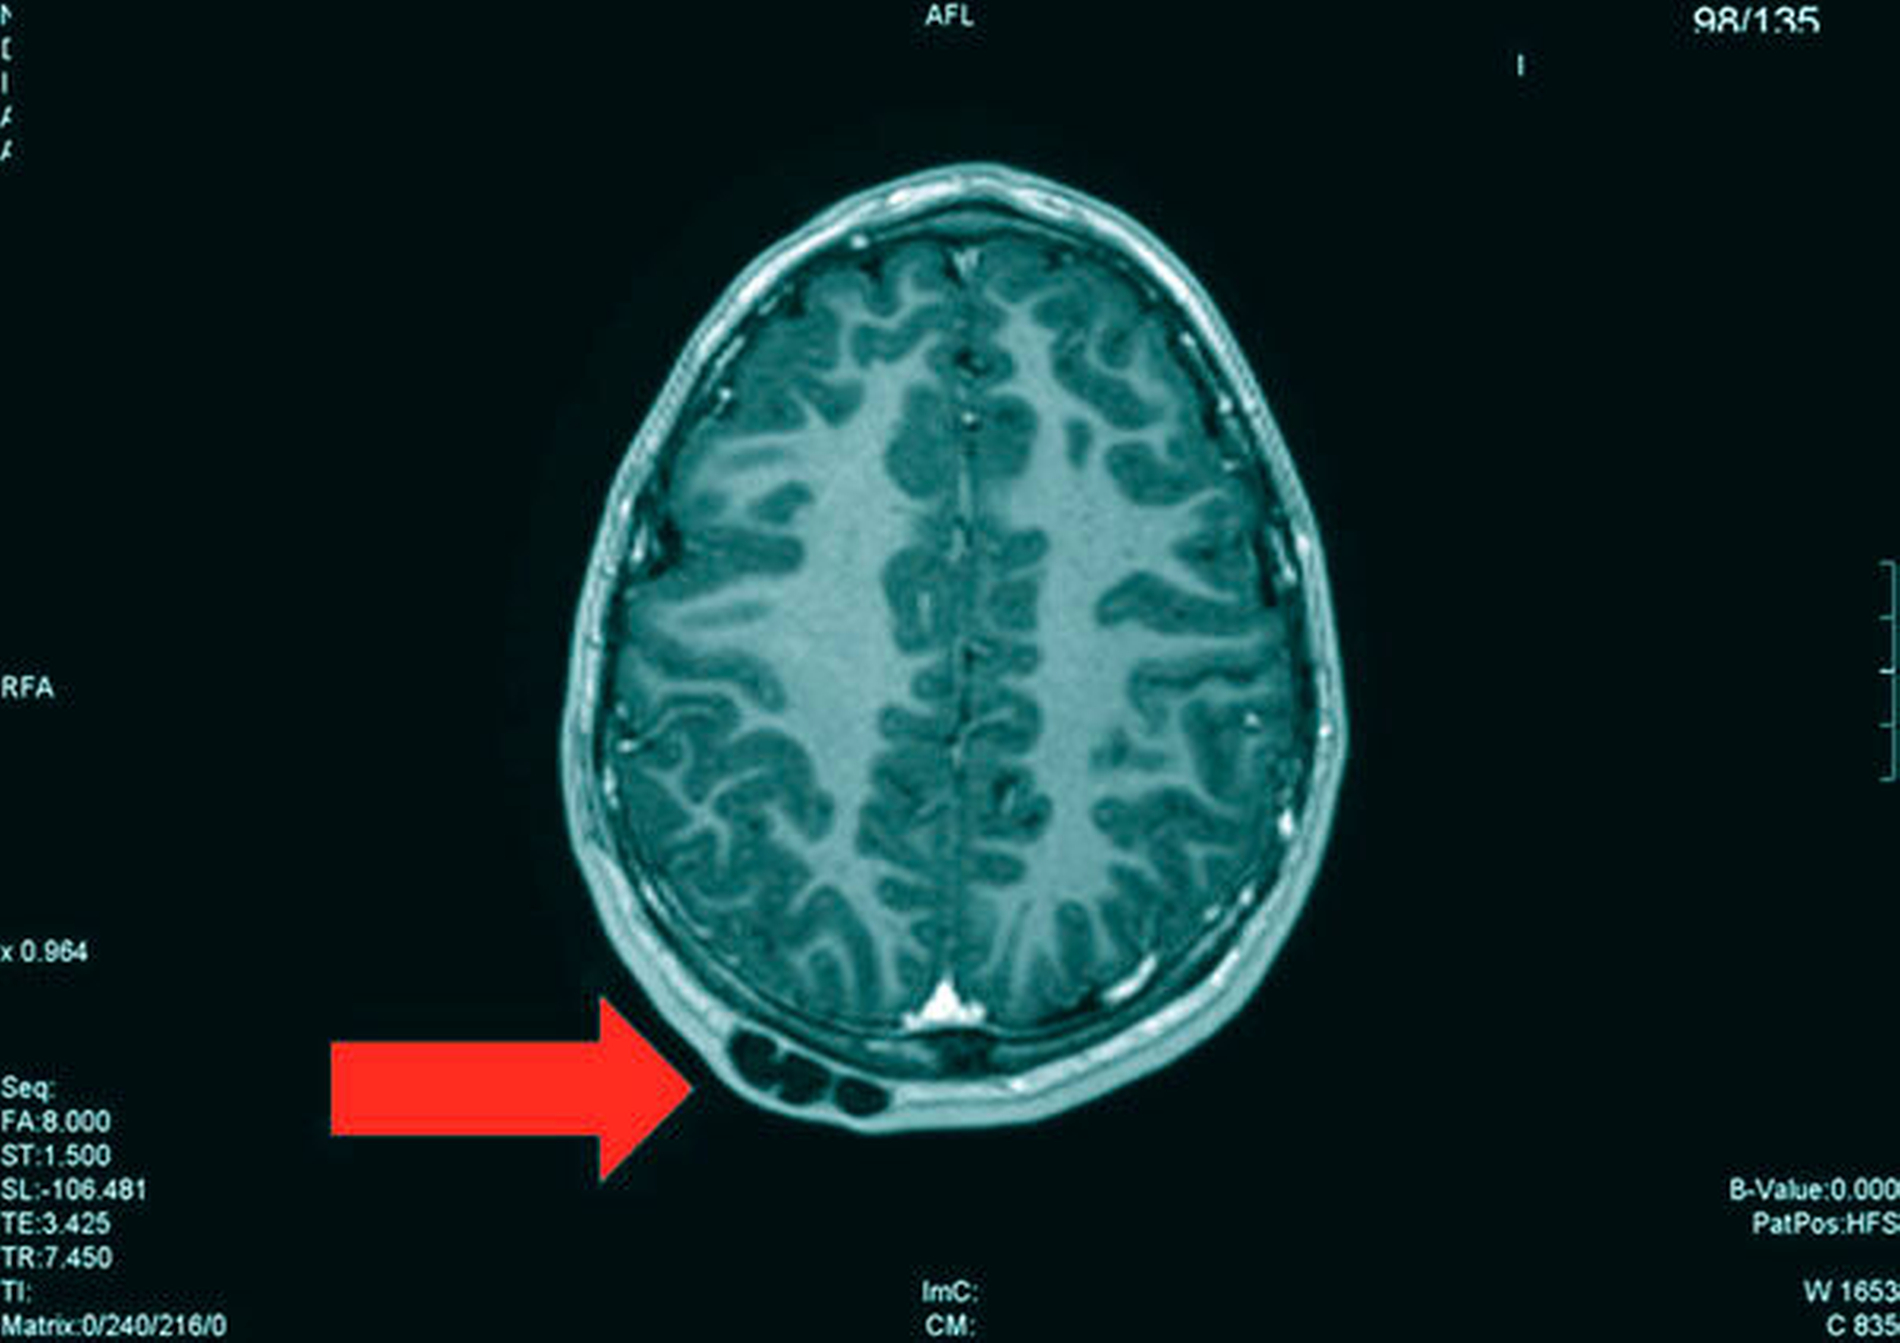

Die Magnetresonanztomografie des Neuro- und des Viszerokraniums erbrachte den Nachweis eines Areals erhöhter Kontrastmittelaufnahme im Bereich des basalen Kieferwinkelrandes links mit einer Ausdehnung von 3,1 cm x 2,3 cm. Im Bereich der behaarten Kopfhaut zeigten sich subkutan T1-hypointense, zum Teil polylobulierte Läsionen mit Verdacht auf epidermale Zysten sowie subgaleale T2-hypointense, flächig kontrastmittelaufnehmende Läsionen mit Verdacht auf Osteome (Abbildungen 3a bis 3d).